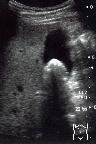

結石

右肋弓下縦走査